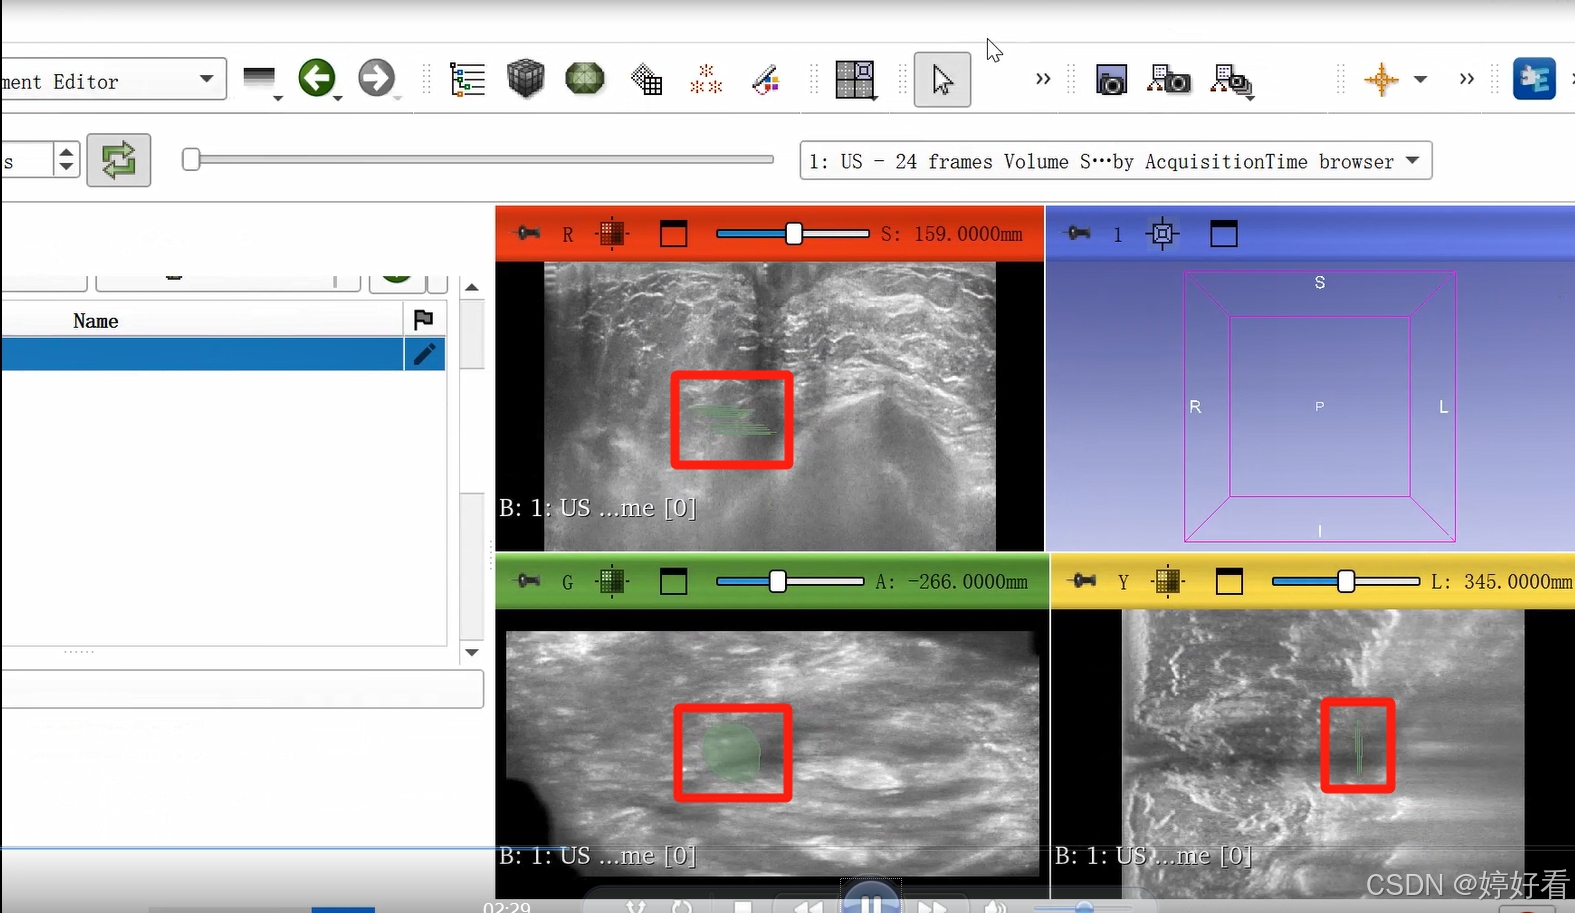

2.3 使用Paint功能勾画感兴趣区域。

可以隔两三层画一次(示例中为随意勾画,大家在实际操作中可以请专业的医生确认感兴趣区域)。

这是一个三维的图像,我们只要在一个面上勾画就可以了,另外两个面会自动显示勾画的区域。

2.4 点击Show 3D,显示三维图像。